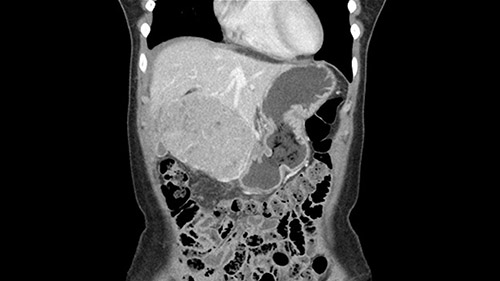

So if we look at the CT scan, on the axial, it’s a larger lesion. It’s about 6 or 7 or 8 centimeters. So it does look a bit threatening in terms of its resectability but if you really drill down deeply into the anatomy, and I think the coronal [imaging] is even better, you can see that the entire mass is on the patient’s left side of the falciform ligament. So it’s really only a left-sided tumor and not even really a left-sided tumor because Segment 4 is uninvolved anatomically.

As I review the CT scan, we have both arterial and venous phases, the tumor is obvious. But I’ll start by saying that the liver itself does not appear to be cirrhotic to my eye. It’s got a normal contour and allied to that, that I do not see evidence of portal hypertension. The spleen is normal, there’s no collateral vessels. The tumor itself, I measured maximally at about 11 centimetres in diameter and I’m told the alpha fetoprotein is very high (over 10000), which is entirely consistent with this being a solitary hepatocellular carcinoma that is very exophytic. It seems to emanate off the inferior margin of Segment 3 (because that’s the falciform). I’ll start by saying that this is not transplantable. The tumor exceeds our guidelines for transplantation, but it's likely resectable based on normal liver and no portal hypertension.

What kind of procedure can we plan for this patient? It obviously has to be a left hemihepatectomy because most of the lesion is actually in Sg4. Can we do something which is less than a hemihepatectomy and just do only a segmental resection? The answer to that is that this vascular supply, if you are trying to ligate only the portal venous pedicle to the Segment 4, it is very close to the tumor and you will end up not having not a great margin as far as tumor resection is concerned so I would recommend a left hemihepatectomy and not just a partial or segmental resection. You can also see that it is crossing the falciform line and going on to Segment 2 and 3 so trying to do anything less than a left hemihepatectomy may not give the right kind of margins which we need for this tumor. Fortunately for us, the contours of the liver, which are very important to see in a Hepatitis B patient, there are no cirrhosis which I can see. The normal liver functions indicate that it's a well compensated Hepatitis B.

The other thing I would do in this case is to certainly to assess the coronal phase as we can see in the coronal phase, this tumor looks like it's growing from Segment 3, and again I don’t think there’s involvement of the right side of the liver or even on Segment 4.